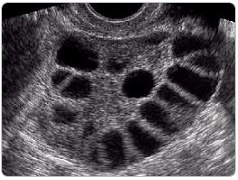

これは、卵巣の中に未成熟な卵胞がたくさん溜まった状態がよく起きることを指します。

1930年代に初めて報告されたときは「小さな嚢胞(のうほう=袋)がたくさんある卵巣」と見えたことから、多嚢胞性卵胞という名がつきました。

ただ、これは“卵子の卵”が途中で成長を止めている状態で、悪性の「腫瘍」や「のう胞」とは異なります。